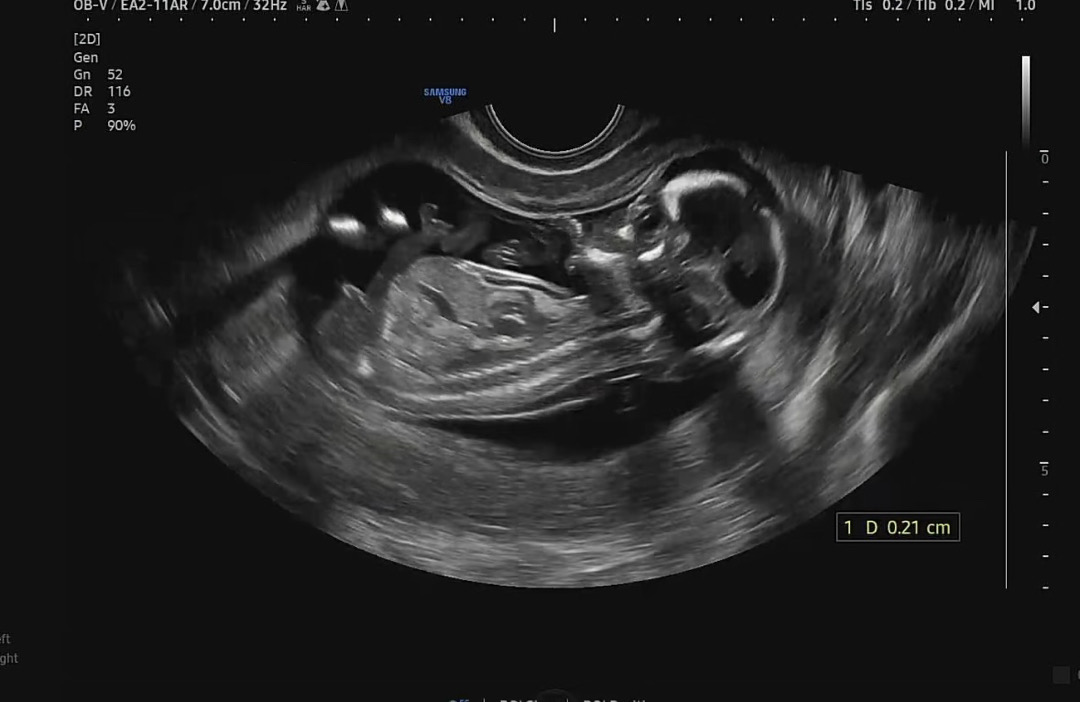

14주 각도법으로 성별 알 수 있을까요?

1차 기형아 검사때 초음파인데 각도법으로 성별 알 수 있을까요?